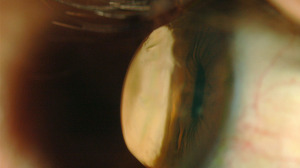

In manchen Fällen, z. B. nach einer schweren Hornhautentzündung kann es notwendig sein, dass die vernarbte Hornhaut durch ein Transplantat ersetzt wird. Aber auch im Falle einer Hornhautverletzung besteht mitunter die Notwendigkeit eines Eingriffes. Wenn das der Fall ist, sprechen wir von Keratoplastik. Ein anderer Ausdruck dafür ist Hornhautplastik.

Auch wenn ein Keratokonus weit fortgeschritten ist und die Vernarbungen der Hornhaut das Sehen dieses Auges so weit herabsetzen, dass das Auge am Sehprozess nur noch wenig oder gar nicht mehr teilnimmt, kann ebenfalls eine Hornhauttransplantation nötig sein.

Eine Keratoplastik Operation dauert in der Regel zwischen 45 und 60 Minuten. Dabei wird die Stelle der vernarbten Hornhaut kreisförmig entfernt. Zudem wird eine gleich große Spenderhornhaut eingenäht. Die Fäden verbleiben für ca. ein Jahr im Auge. Dann werden sie entfernt.